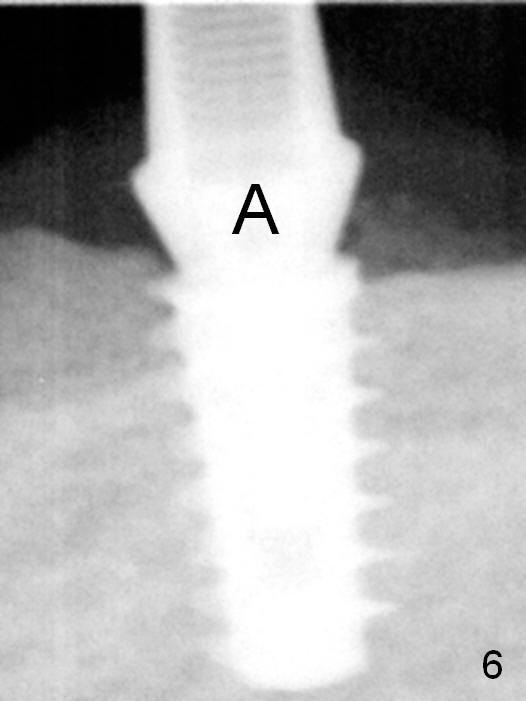

A 5x9 mm implant is placed with a pair abutment (A) to test the trajectory (Fig.6). The implant appears to have osteointegrated 2 months postop (Fig.9 with a healing abutment). There is no bone resorption 1 year 4 months post cementation (Fig.16). The implant remains stable 3.5 years post cementation (in spite of open margin), while the other abutment for the RPD (the tooth #30) has mobility with gingival recession.